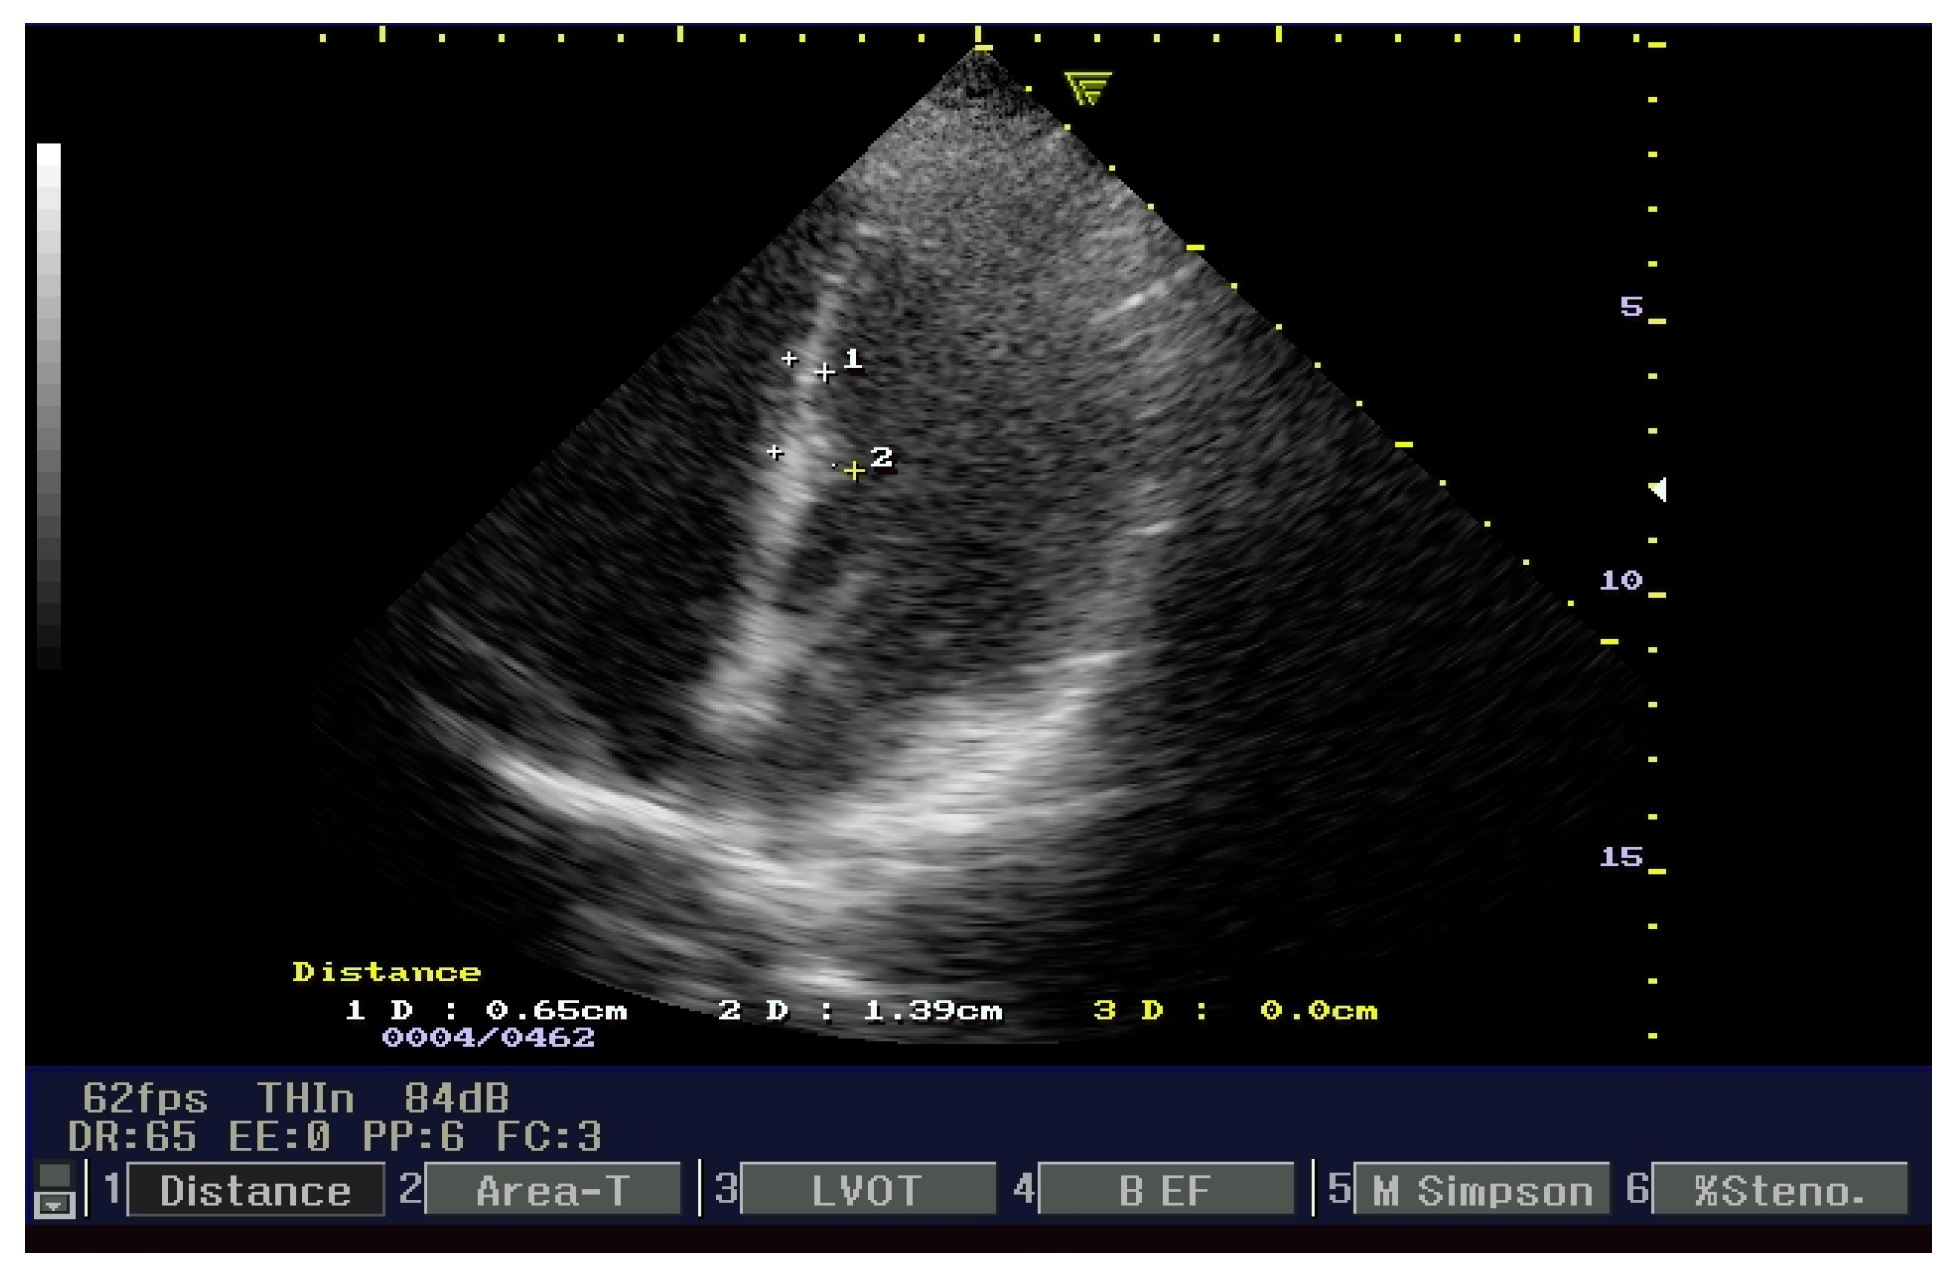

3.2.2. Echocardiogram